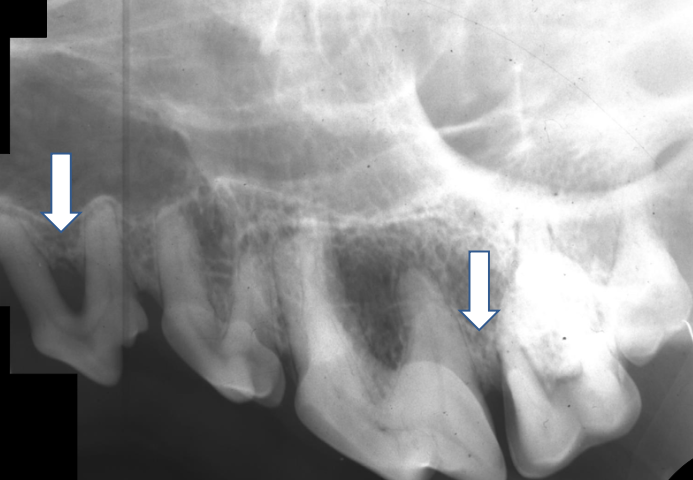

Quelles sont les lx?

Perte osseuse sur 404 et poche infra-osseuse sur 304